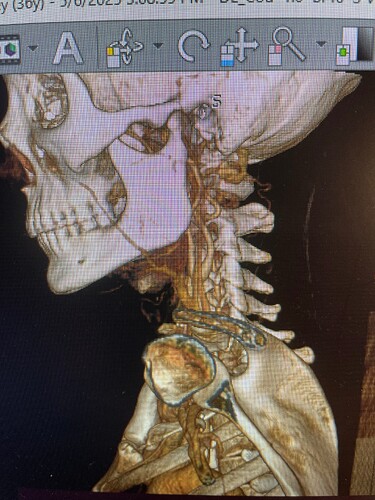

I figured out how to download the radiantviewer and open my images in it, is the styloid ligament in these pics? The left side is for sure all jumbled looking…thank you for any input!

@Coco1 - In the first of the 3 images you posted, it looks like your left ICA does a partial wrap around your C1. It’s already small coming out of your skull, does the wrap then gets even smaller. I can’t see much of your left IJV on the front side.

Your stylohyoid ligaments aren’t visible in the images you posted because your mandible is in the way in the two images where we should be able to see them. If you can get an angle that looks under the jaw or if you can cut away the jaw so we can see what’s behind it, that would allow us to see your calcified s-h ligaments better.

The circled area is where it looks like the IJV is partially wrapped around your C1 on the left side.